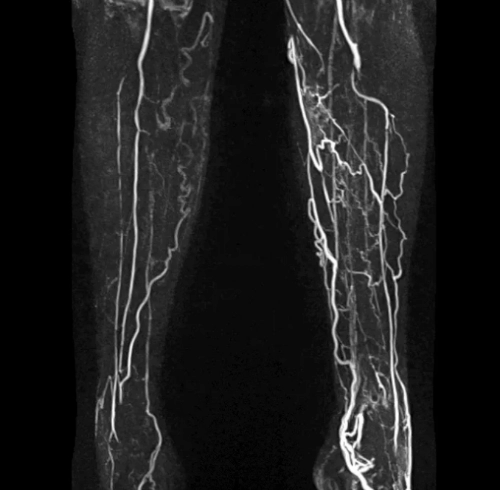

КТ сосудовНаиболее точной и эффективной диагностической методикой для выявления патологий кровеносной системы сегодня служит КТ сосудов. Исследование, которое нередко называют КТ-ангиографией, представляет собой послойное сканирование организма пациента слабым рентгеновским излучением. Последующая компьютерная обработка позволяет получать плоские и трехмерные изображения сосудистой системы головного мозга, шейной области, конечностей, коронарной зоны либо всего организма в целом. Высокая разрешающая способность оборудования позволяет обнаруживать аномальные участки и патологические изменения даже на самых ранних стадиях развития.

Для исследований используются мультиспиральные томографы Revolution CT и Somatom Definition, обеспечивающие высочайшую точность и информативность результатов в любой области кровеносной системы. Отсутствуют ограничения по весу пациентов. Минимальная лучевая нагрузка позволяет при необходимости проводить повторную диагностику с недельным интервалом.